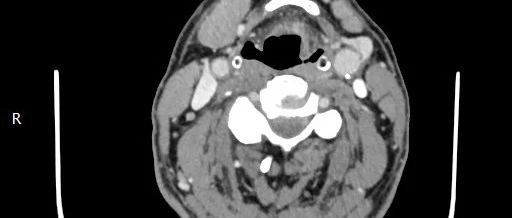

患者,男,37岁,菜农。2016年4月发现口内两侧颊部各有1个肿物,无疼痛等不适,1周后左侧颊部肿物自行消失,右颊部肿物至7月份明显增大,遂于7月23

乳腺隆突性皮肤纤维肉瘤影像表现2例并文献复习